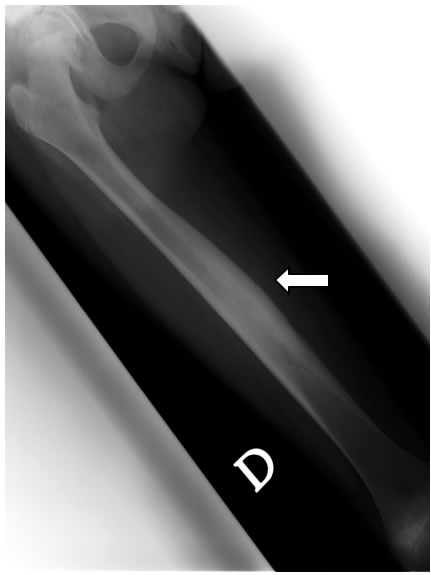

A distanza di un anno (2004) C. ritorna nuovamente alla nostra attenzione per la comparsa di febbricola accompagnata da dolori agli arti inferiori, in particolare a destra, con indici di flogosi aumentati e rilievo obiettivo di sfumato deficit di forza all'arto inferiore destro, su base antalgica .L'ecografia e la radiografia dell'arto inferiore destro mostrano rispettivamente un minimo versamento articolare a livello della coxo-femorale e un aspetto del femore, sempre a destra, di marcato ispessimento della corticale ossea, come da reazione periostale, con una relativa iperdiafania della spongiosa. (figura 2)

Figura 2: radiogramma del femore che mostra, al III medio, marcato aumento di spessore della corticale ossea sul versante interno